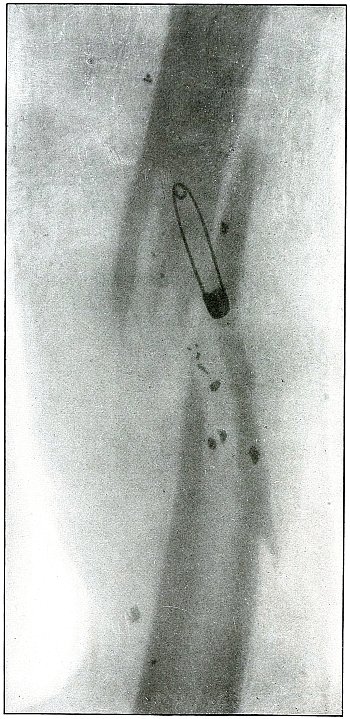

Rifle—Plate 65.

Gunshot Fracture of the Tibia.

The course of the bullet was transverse, from within outward, striking the bone near the outer border with the velocity of mid or long range, producing long fissures without separation of fragments.

The safety pin, of course, lies in the dressings and on the side away from the plate, as shown by its somewhat indefinite outline and increased length.

The wounds of entrance and exit are practically the same.

The treatment in such cases is that of a simple fracture, except for the management of an occasional infection, and the results are favorable. [Pg 142]